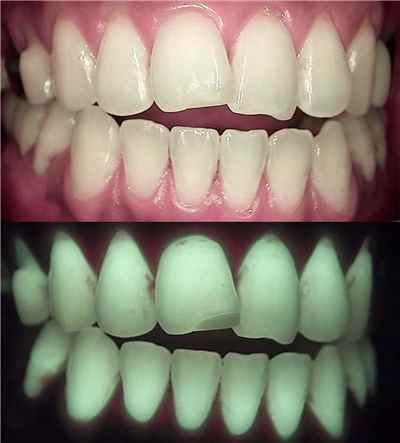

여드름 치료를 위해서 미노사이클린 복용으로 약간 파랗게 변색된 치아 (출처: Lee Ann Brady DMD)